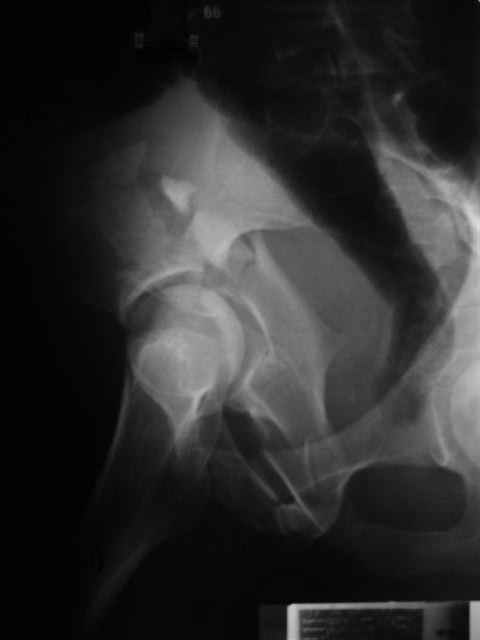

Спасибо за комментарии и рекомендации. Откровенно говоря, больного я прооперировал на прошлой неделе, через 5 дней после аварии и проблем с ним пока никаких нет, на удивление при достаточно обширной диссекции (илиофеморальный доступ) болей практически нет, так что больной самостоятельно садится в кровати, выполняет активные движения в оперированном суставе, сгибая до 60 градусов пока, далее с ассистенцией.

Причиной обращения к сообществу были возникшие непосредственно после операции сомнения и разочарования полученным качеством репозиции: а надо ли было трогать перелом вообще, репозиция передней колонны технически была очень сложна для меня, хотя реконструкции была в той же последовательности, что Д-р А.В.Рунков рекомендовал, в какой-то момент безуспешных манипуляций стал думать о *вторичной конгруэнтности*, которую не так давно обсуждали на

форуме и скелетном вытяжении. С репозицией и фиксацией задней колонны и отдельно задне-верхней стенки впадины проблем не возникло. Послеоп. Рг граммы в приложении. Если возникнут какие-либо дополнения или поправки - был бы признателен.